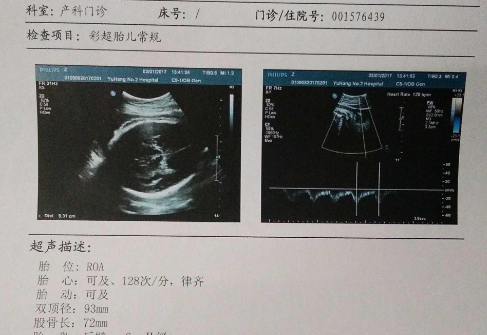

1、看胎心

所谓胎心就是指胎儿的心跳速度,可以买一个胎心检测仪进行检测。当发现胎儿的心率小于140次/分钟的时候,有可能怀的就是男宝哦!相反,如果测出宝宝的心跳大于140次/分钟的时候,那么宝宝就有可能是个小公主。